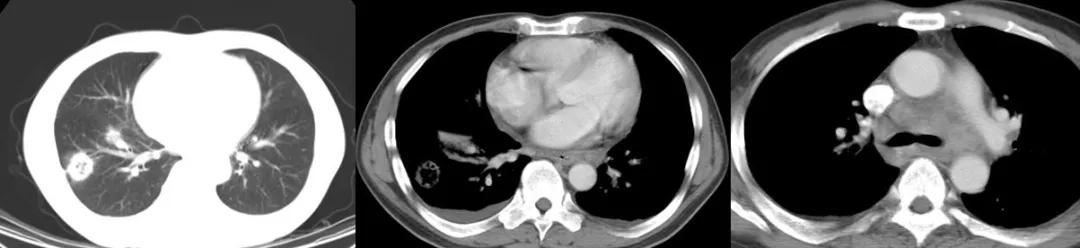

二、这是典型肺结核X线诊断特征:

目前的最新分类为:Ⅰ型: 原发综合征; Ⅱ型: 血行播散型; Ⅲ型: 继发性肺结核 (浸润性肺结核,空洞性肺结核,结核球,干酪样肺炎,纤维空洞型肺结核等); Ⅳ型: 结核性胸膜炎。

从影像学上,有可能表现为Ⅲ型继发性肺结核,也有可能更像原发综合征——有肺部淋巴结肿大、有肺内实质的浸润等等。

还有单一的结核球改变,看了影像后应不太会忘记。(卫星灶 2~4cm,多小于3cm)

经过治疗以后明显吸收好转:

病例7:

患者是混合性结缔组织疾病,激素治疗6个月后出现发热,肺部病灶明显增多,两侧情况不一样,我们冒了很大风险给他做支气管肺泡灌洗,做刷检、做活检,刷检时也找到了抗酸杆菌,但活检的结果是:既有一般的结缔组织的肉芽肿性改变,同时也看到有结核的干酪样坏死。因为患者是在激素减量过程中出现的症状,所以我们考虑是既有结缔组织疾病,又合并了肺结核。

所以,在免疫功能低下、有基础疾病的人群当中,肺部出现病灶,有呼吸系统的症状或有发热,我们鉴别诊断的时候就不能想得那么简单,有时并不是一元论,有时是会出现 混合感染 ,结核可能合并普通细菌感染,也可以和真菌、巨细胞病毒合并呈现,因为在患者免疫功能低下时,很多条件致病菌可以同时出现,肺结核也不例外。